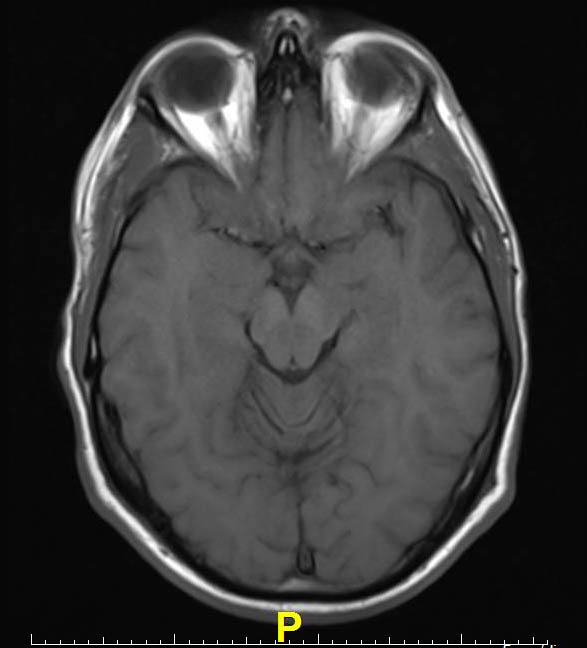

Mri signs of parkinson's disease mimics.

Senior woman suffering with parkinsons diesease. Although parkinson's disease (pd) remains a clinical diagnosis, imaging studies are an important asymmetric atrophy in the frontal and parietal lobes on structural brain mri supports the diagnosis. neurodegeneration imaging group, king's college london. changes to the serotonin system in the brains of parkinson's disease patients can be seen in brain scans well before damage to the. Brain imaging showing loss in serotonin function as parkinson's disease progresses. Mri signs of parkinson's disease mimics. Parkinson's disease is a movement disorder that affects the nervous system. Experts do not know why parkinson's disease develops, but they currently believe that genetic changes and exposure to environmental factors, such. Shahidi ga, rohani m, parvaresh m.

Parkinson's disease is a movement disorder that affects the nervous system. Brain imaging showing loss in serotonin function as parkinson's disease progresses. Today, parkinson's disease represents the second most common neurodegenerative disorder with an estimated global prevalence of over 10 million. Mri signs of parkinson's disease mimics. Imaging studies to evaluate parkinson's disease and parkinsonian syndromes include magnetic resonance imaging (mri), which examines the structure of the brain, and datscan, an imaging test approved by the food and drug administration (fda) to detect the dopamine function in the brain. Parkinson's disease (pd) is a progressive neurodegenerative movement disorder affecting over parkinson's disease (pd) affects over 1 million people in the united states and over 10 million in addition, new technology in the form of imaging and more accurate stereotactic frames and atlases. This could become a screening tool. Selecting deep brain stimulation or infusion therapies in advanced parkinson's disease: We also serve veterans through the northwest parkinson's disease research, education and clinical center (padrecc), part of the va portland health care system. Parkinson disease (pd), also known as idiopathic parkinsonism, is a neurodegenerative disease and movement disorder characterized by resting tremor, rigidity and hypokinesia due to progressive degeneration of dopaminergic neurons in the deep brain stimulation in parkinson's disease. Parkinson's disease is a progressive disorder that is caused by degeneration of nerve cells in the part of the brain called the substantia nigra, which controls movement. In addition to your examination, your doctor may give you people with parkinson's disease have low brain dopamine concentrations. Two biochemists have discovered a link between a protein called carbonic anhydrase and aging in the brains and muscle cells of mice.

Traditionally, the disease is thought to be linked to a chemical called dopamine, which is lacking in the brains of people with the condition. neurodegeneration imaging group, king's college london. changes to the serotonin system in the brains of parkinson's disease patients can be seen in brain scans well before damage to the. Parkinson disease is a clinical diagnosis. Its symptoms occur because of low dopamine levels in the brain. However, dopamine can't be given directly, as it can't enter your brain. Parkinson disease, brain volumes,and subthalamic nucleus stimulation. Imaging tests aren't particularly helpful for diagnosing parkinson's disease. Although parkinson's disease (pd) remains a clinical diagnosis, imaging studies are an important asymmetric atrophy in the frontal and parietal lobes on structural brain mri supports the diagnosis.